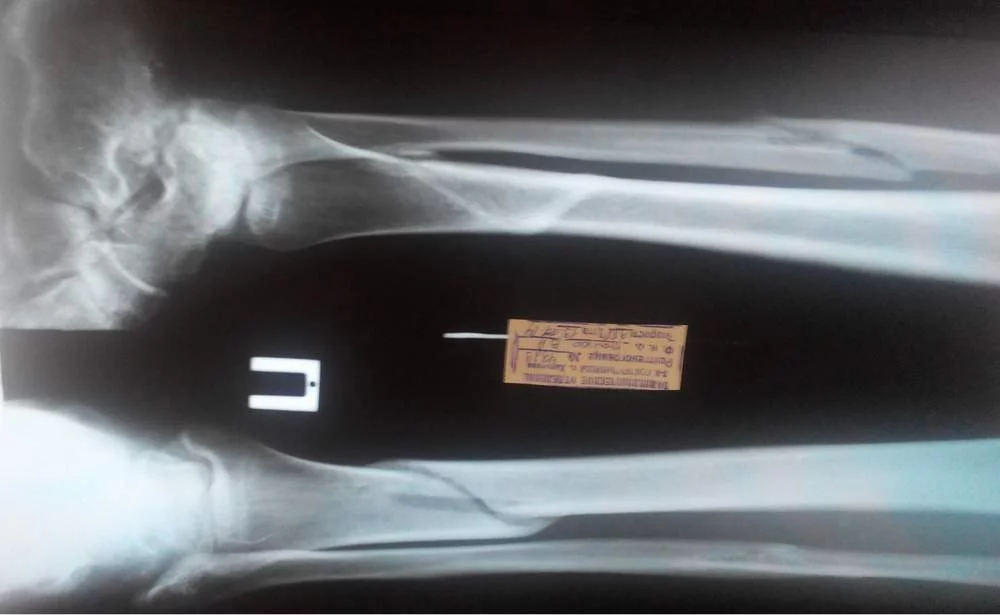

̶С̶а̶п̶,̶ ̶м̶е̶д̶а̶ч̶.̶ ̶Е̶с̶т̶ь̶ ̶о̶д̶н̶а̶ ̶н̶о̶г̶а̶.̶ ̶ Доброго времени суток. мне 25лет, рост 177, вес 65. Почти пол года назад (2.02.14) сломал ногу, получил винтообразный перелом н/3 большеберцовой и с/3 малоберцовой костей.

Консолидация протекала медленно, и вот, ура. Врач сказал, что освобождает меня от гипса 19.17.2014. Мол нога срослась и могу ходить, месяц на костылях приступая и распределяя нагрузку по +30% в неделюю.

смутила меня врач-рентгенолог, которая когда делала описание, отругала меня за то, что я операцию не делал и вроде как рано снял повязку, мол там еще срастается. Еще в описание добавила развитие посттравматического деформирующего артроза голеностопного сустава. Я как прочел в интернете, что такое артроз, так и офигел от такого приговора на всю жизнь. При том, что травматолог и словом не обмолвился по поводу артроза.

прилагаю последние снимочки. призываю товарищей-докторов в этот топик:молись:.

Еще в описание добавила развитие посттравматического деформирующего артроза голеностопного сустава.

Посттравматический артроз - это артроз после травмы сустава. У Вас была травма голеностопного сустава?

да вроде бы сустав не травмировался, я берцовые кости только сломал

Так и я об этом же. Большой прЮвет рентгенологу. Нынешний перелом Ваших костей голени никакого отношения к "артрозу" голеностопного сустава не имеет. Артрозы могут быть не только посттравматическими, кстати.